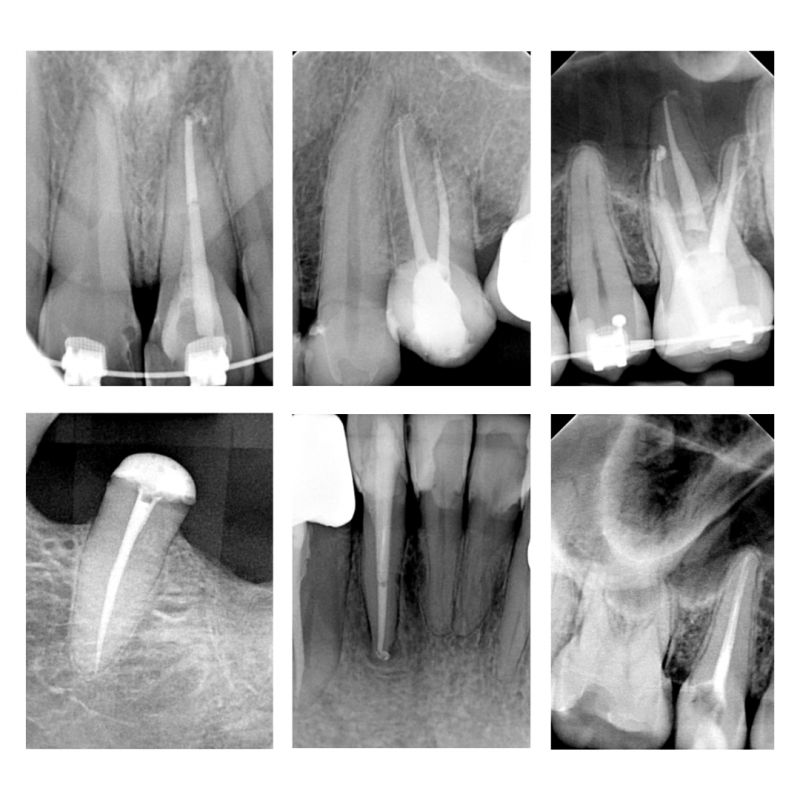

Stan przed i po leczeniu powtórnym kanałowym zęba. Dzięki wykorzystaniu mikroskopu stomatologicznego usunięto złamane narzędzie, udrożniono oraz wypełniono kanały korzeniowe zęba.